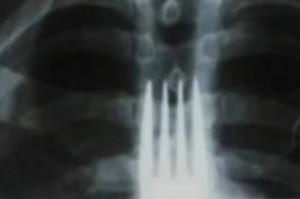

En su intento por terminar con la picazón, el paranaense se tragó un tenedor mientras ingería algunos alimentos. El hombre explicó que la comezón fue tal que el bocado de comida y el utensilio terminaron en el esófago. Para poder extraer el objeto, debió ser intervenido y se recupera favorablemente, señala O Globo.

El cirujado a cargo de la operación, Júlio Mascarenhas de Souza, dijo que es común tragarse cosas en accidentes domésticos, pero que es la primera vez que tiene que extirpar un tenedor.